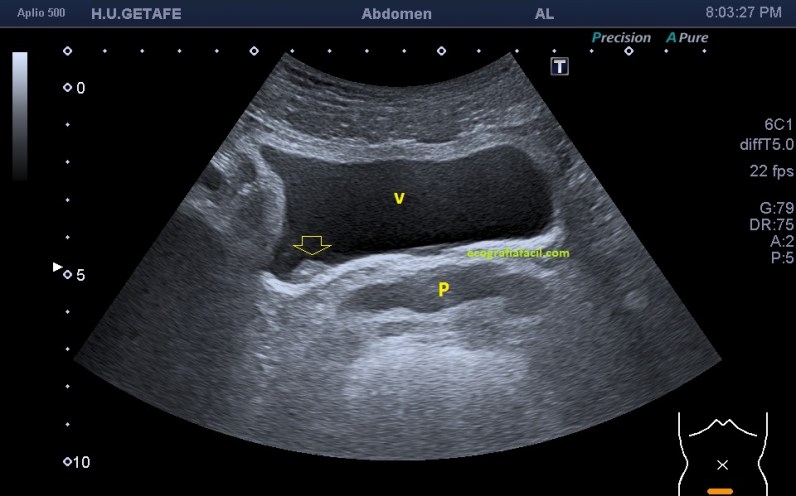

Al final del estudio llegué a la imagen de una vejiga sin repleción que me servía para realizar medida de la próstata, pero cuando estaba revisando el órgano en cuestión me dió mala espina una casi inapreciable alteración de la pared de la vejiga, podía ser perfectamente un defecto de la pared al no estar la vejiga replecionada, pero le pedí rellenar la vejiga, y cuando el paciente me avisó que tenía ganas de orinar, le volví a pasar y encontré lo que os comento a continuación.

Observa como cambia todo entre la imagen 1 y 2, marcando la flecha amarilla el mismo lugar y la variación sustancial de como se ve una lesión en una vejiga distendida y en otra que no lo está, ojo que estas situaciones son cotidianas y el paciente puede ser asintomático.